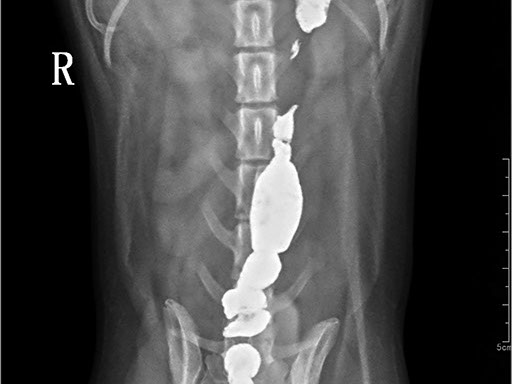

Коллиматорный прицел формирует пучок рентгеновского излучения на участок исследования. Проходя через ткани тела, излучение попадает на плоскопанельный цифровой детектор, который, в свою очередь, передает сигналы на компьютер.

В считанные секунды полученные данные обрабатываются компьютером посредством установленной на него программы визуализации, и сформированное клиническое изображение выводится на монитор лаборанта.

Клинические изображения (снимки) можно напечатать на принтере, сохранить в архиве или отправить по сети коллегам для оперативного консилиума.

Цифровая рентгеновская установка ASR-6150C поставляется с мобильным столом пациента и комплектом рентгенопрозрачных анатомических ложементов всех размеров, видов и пород домашних животных.